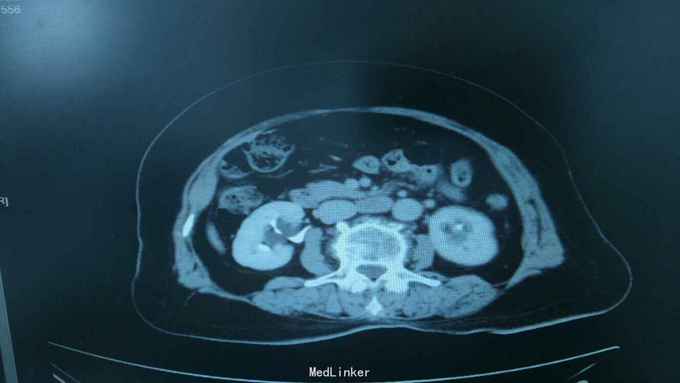

68岁,女性。 主诉:左侧腰痛1年,加重1个月。 病史:1年前无明显诱因出现左侧腰痛,无恶心呕吐,无肉眼血尿。1个月前加重,于外院查泌尿系彩超显示:左肾积液,输尿管显示不清。

诊断:双肾盂旁囊肿 治疗:因患者肾盂未明显受压,疼痛症状不明显,等待观察,暂未予处理。

双侧同时出现的病例并不多见,临床只能通过泌尿系统CTU或增强CT加以鉴别,彩超无法区分肾盂积水及盂旁囊肿。